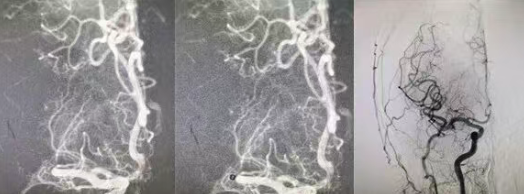

生死競(jìng)速!國(guó)文醫(yī)院神經(jīng)外科團(tuán)隊(duì)兩次手術(shù)挽救顱腦重?fù)p傷患者生命

人生無(wú)常,世事難料。一場(chǎng)外出游玩,竟然被突如其來(lái)的意外改寫(xiě)了人生軌跡——年輕的患者意外摔傷了頭部,劇烈的沖擊造成嚴(yán)重顱腦損傷,他的生命體征急速下滑,如同風(fēng)中殘燭般岌岌可危。家人的呼救聲里滿(mǎn)是絕望,緊急送醫(yī)的路上,時(shí)間每一秒都在與生命賽跑,最終,國(guó)文醫(yī)院成了這場(chǎng)生死救援的“起點(diǎn)線”。 閱讀量:600